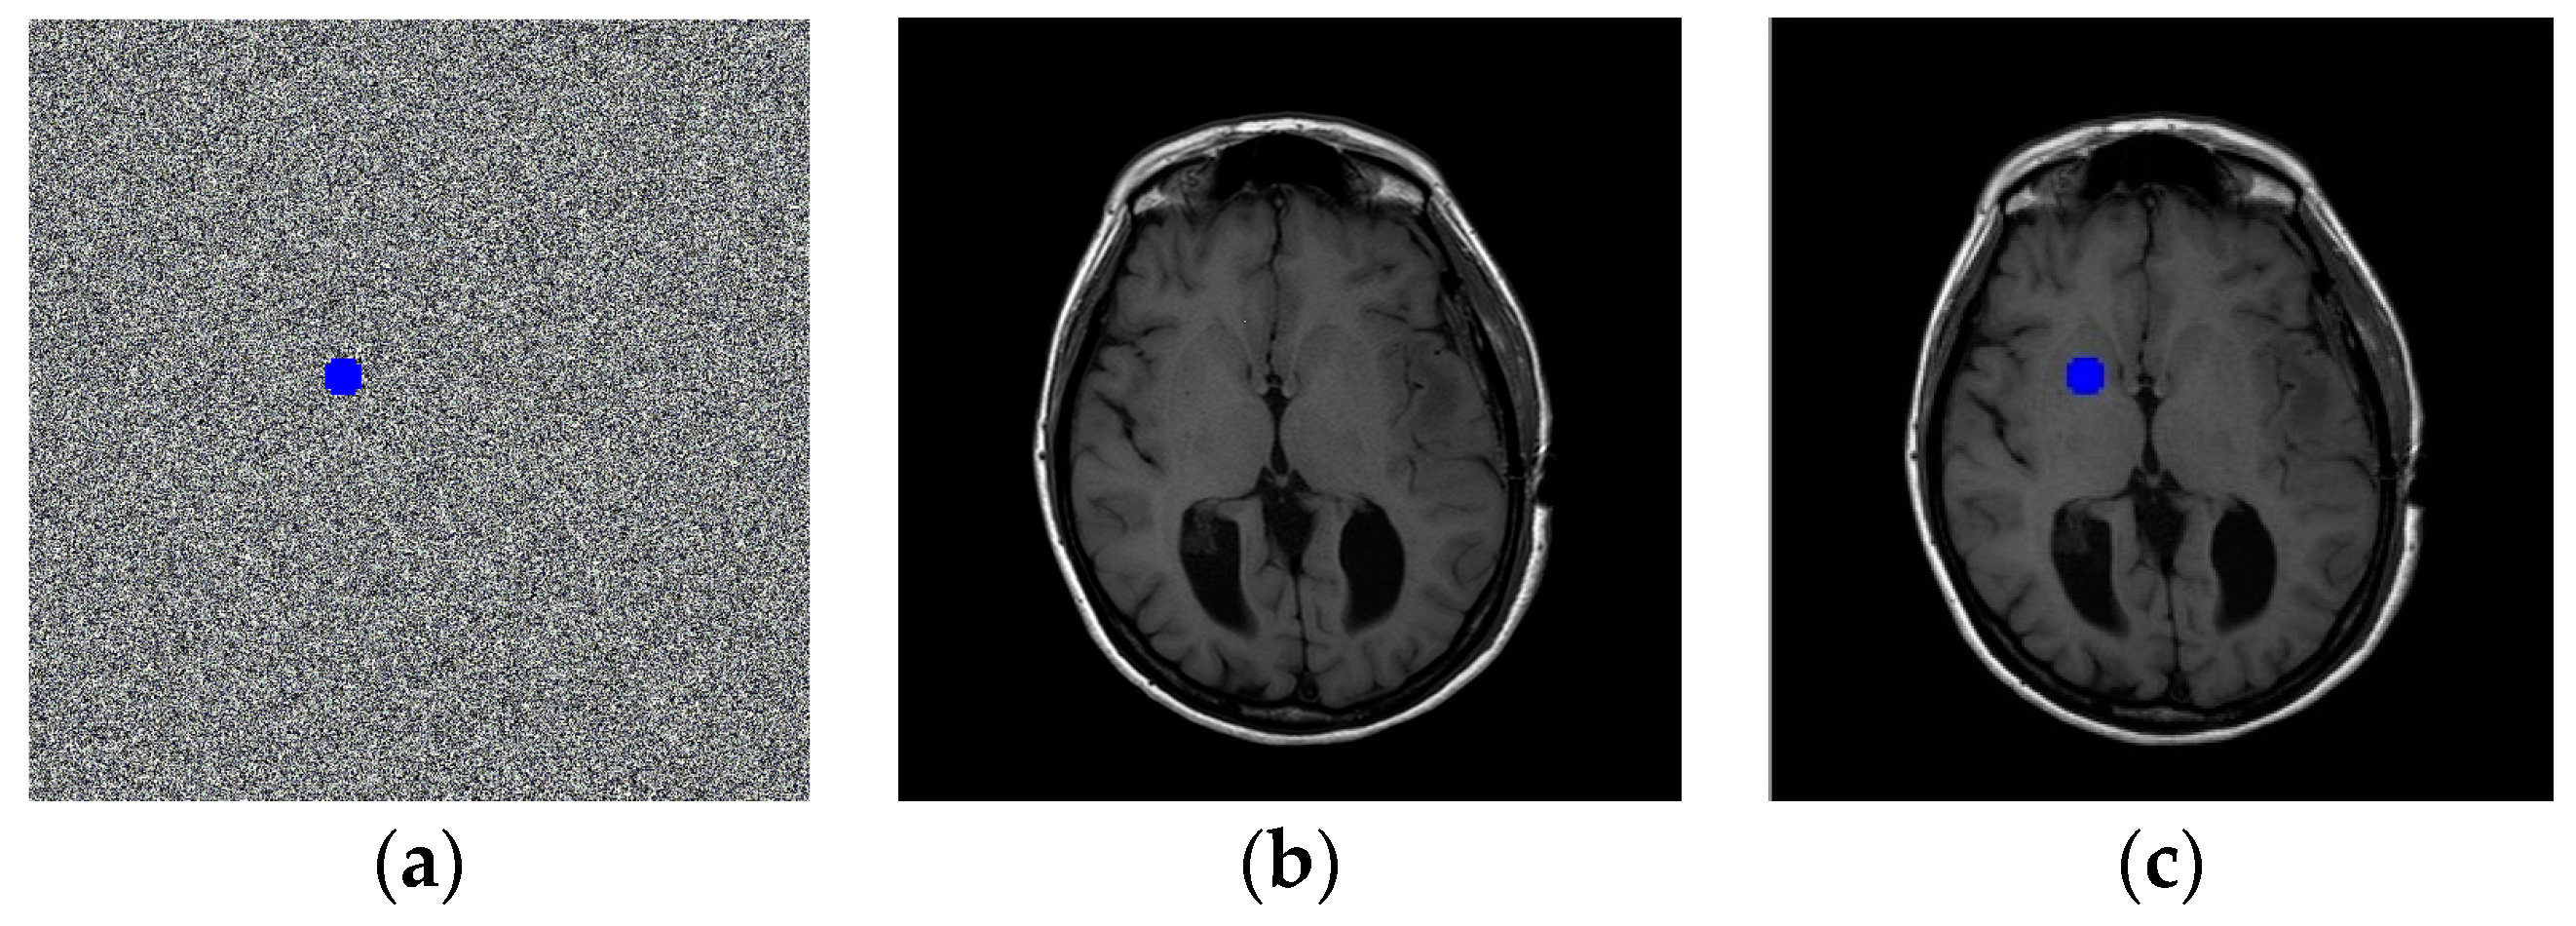

| Image | IM-0001-0004 | IM-0001-0010 | IM-0001-0012 | IM-0001-0014 | IM-0001-0019 | IM-0002-0022 |

| UACI | 0.3355 | 0.3339 | 0.3348 | 0.3343 | 0.3343 | 0.3351 |

| NPCR | 0.9961 | 0.9960 | 0.9959 | 0.9961 | 0.9961 | 0.9964 |

| Image | Sharing secret | Horizontal | Vertical | Diagonal |

| IM-0001-0004 | Sharing secret 1 | -0.0056 | -0.0073 | -0.0024 |

| Sharing secret 2 | -0.0011 | -0.0096 | -0.0107 | |

| IM-0001-0010 | Sharing secret 1 | -0.0105 | -0.0128 | 0.0198 |

| Sharing secret 2 | -0.01232 | 0.0016 | 0.0110 | |

| IM-0001-0012 | Sharing secret 1 | -0.0085 | -0.0131 | 0.0011 |

| Sharing secret 2 | -0.0016 | 0.0044 | 0.0001 | |

| IM-0001-0014 | Sharing secret 1 | -0.0217 | 0.0031 | -0.0026 |

| Sharing secret 2 | -0.0067 | 0.0088 | -0.0028 | |

| IM-0001-0019 | Sharing secret 1 | 0.0073 | -0.0022 | -0.0053 |

| Sharing secret 2 | 0.0021 | 0.0039 | 0.0011 | |

| IM-0001-0022 | Sharing secret 1 | 0.0018 | -0.0213 | 0.0016 |

| Sharing secret 2 | 0.0026 | -0.0136 | -0.0029 |